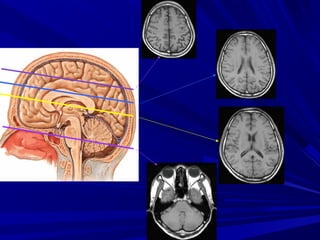

GIAÛI PHAÃU TREÂN CAÙC LÔÙP CAÉTGIAÛI PHAÃU TREÂN CAÙC LÔÙP CAÉT

DUØNG HEÄ THOÁNG NAÕO THAÁTDUØNG HEÄ THOÁNG NAÕO THAÁT

LAØM MOÁC:LAØM MOÁC:

 Naõo thaát beân.Naõo thaát beân.

 Naõo thaát III.Naõo thaát III.

 Naõo thaát IV.Naõo thaát IV.

 Dòch naõo tuûy & caùc beåDòch naõo tuûy & caùc beå

naõonaõo

HEÄ THOÁNG NAÕOHEÄ THOÁNG NAÕO

THAÁTTHAÁT

Cắt qua não thất IV

Cắt qua não thất III

Cắt qua thân

não thất bên

Cắt qua trên